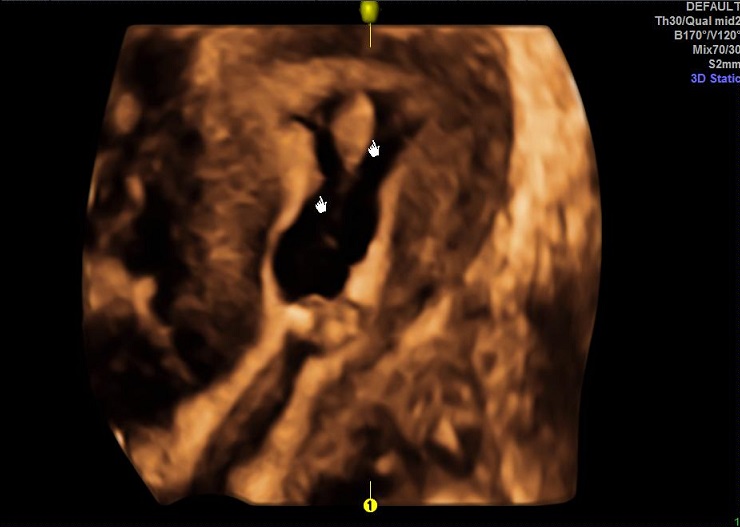

女性,30岁,继发性不孕1年余,有人流史。常规二维超声宫腔线清晰,中段内膜回声略不均匀。宫腔三维显示:宫腔呈倒三角形,宫角锐利,体部内膜可见小片偏高回声区。宫腔水造影显示:体部宫腔后壁数处不规则突起及条形低回声带。子宫输卵管实时三维超声造影显示:宫腔中部不规则充盈缺失。诊断:宫腔粘连,子宫内膜增生。